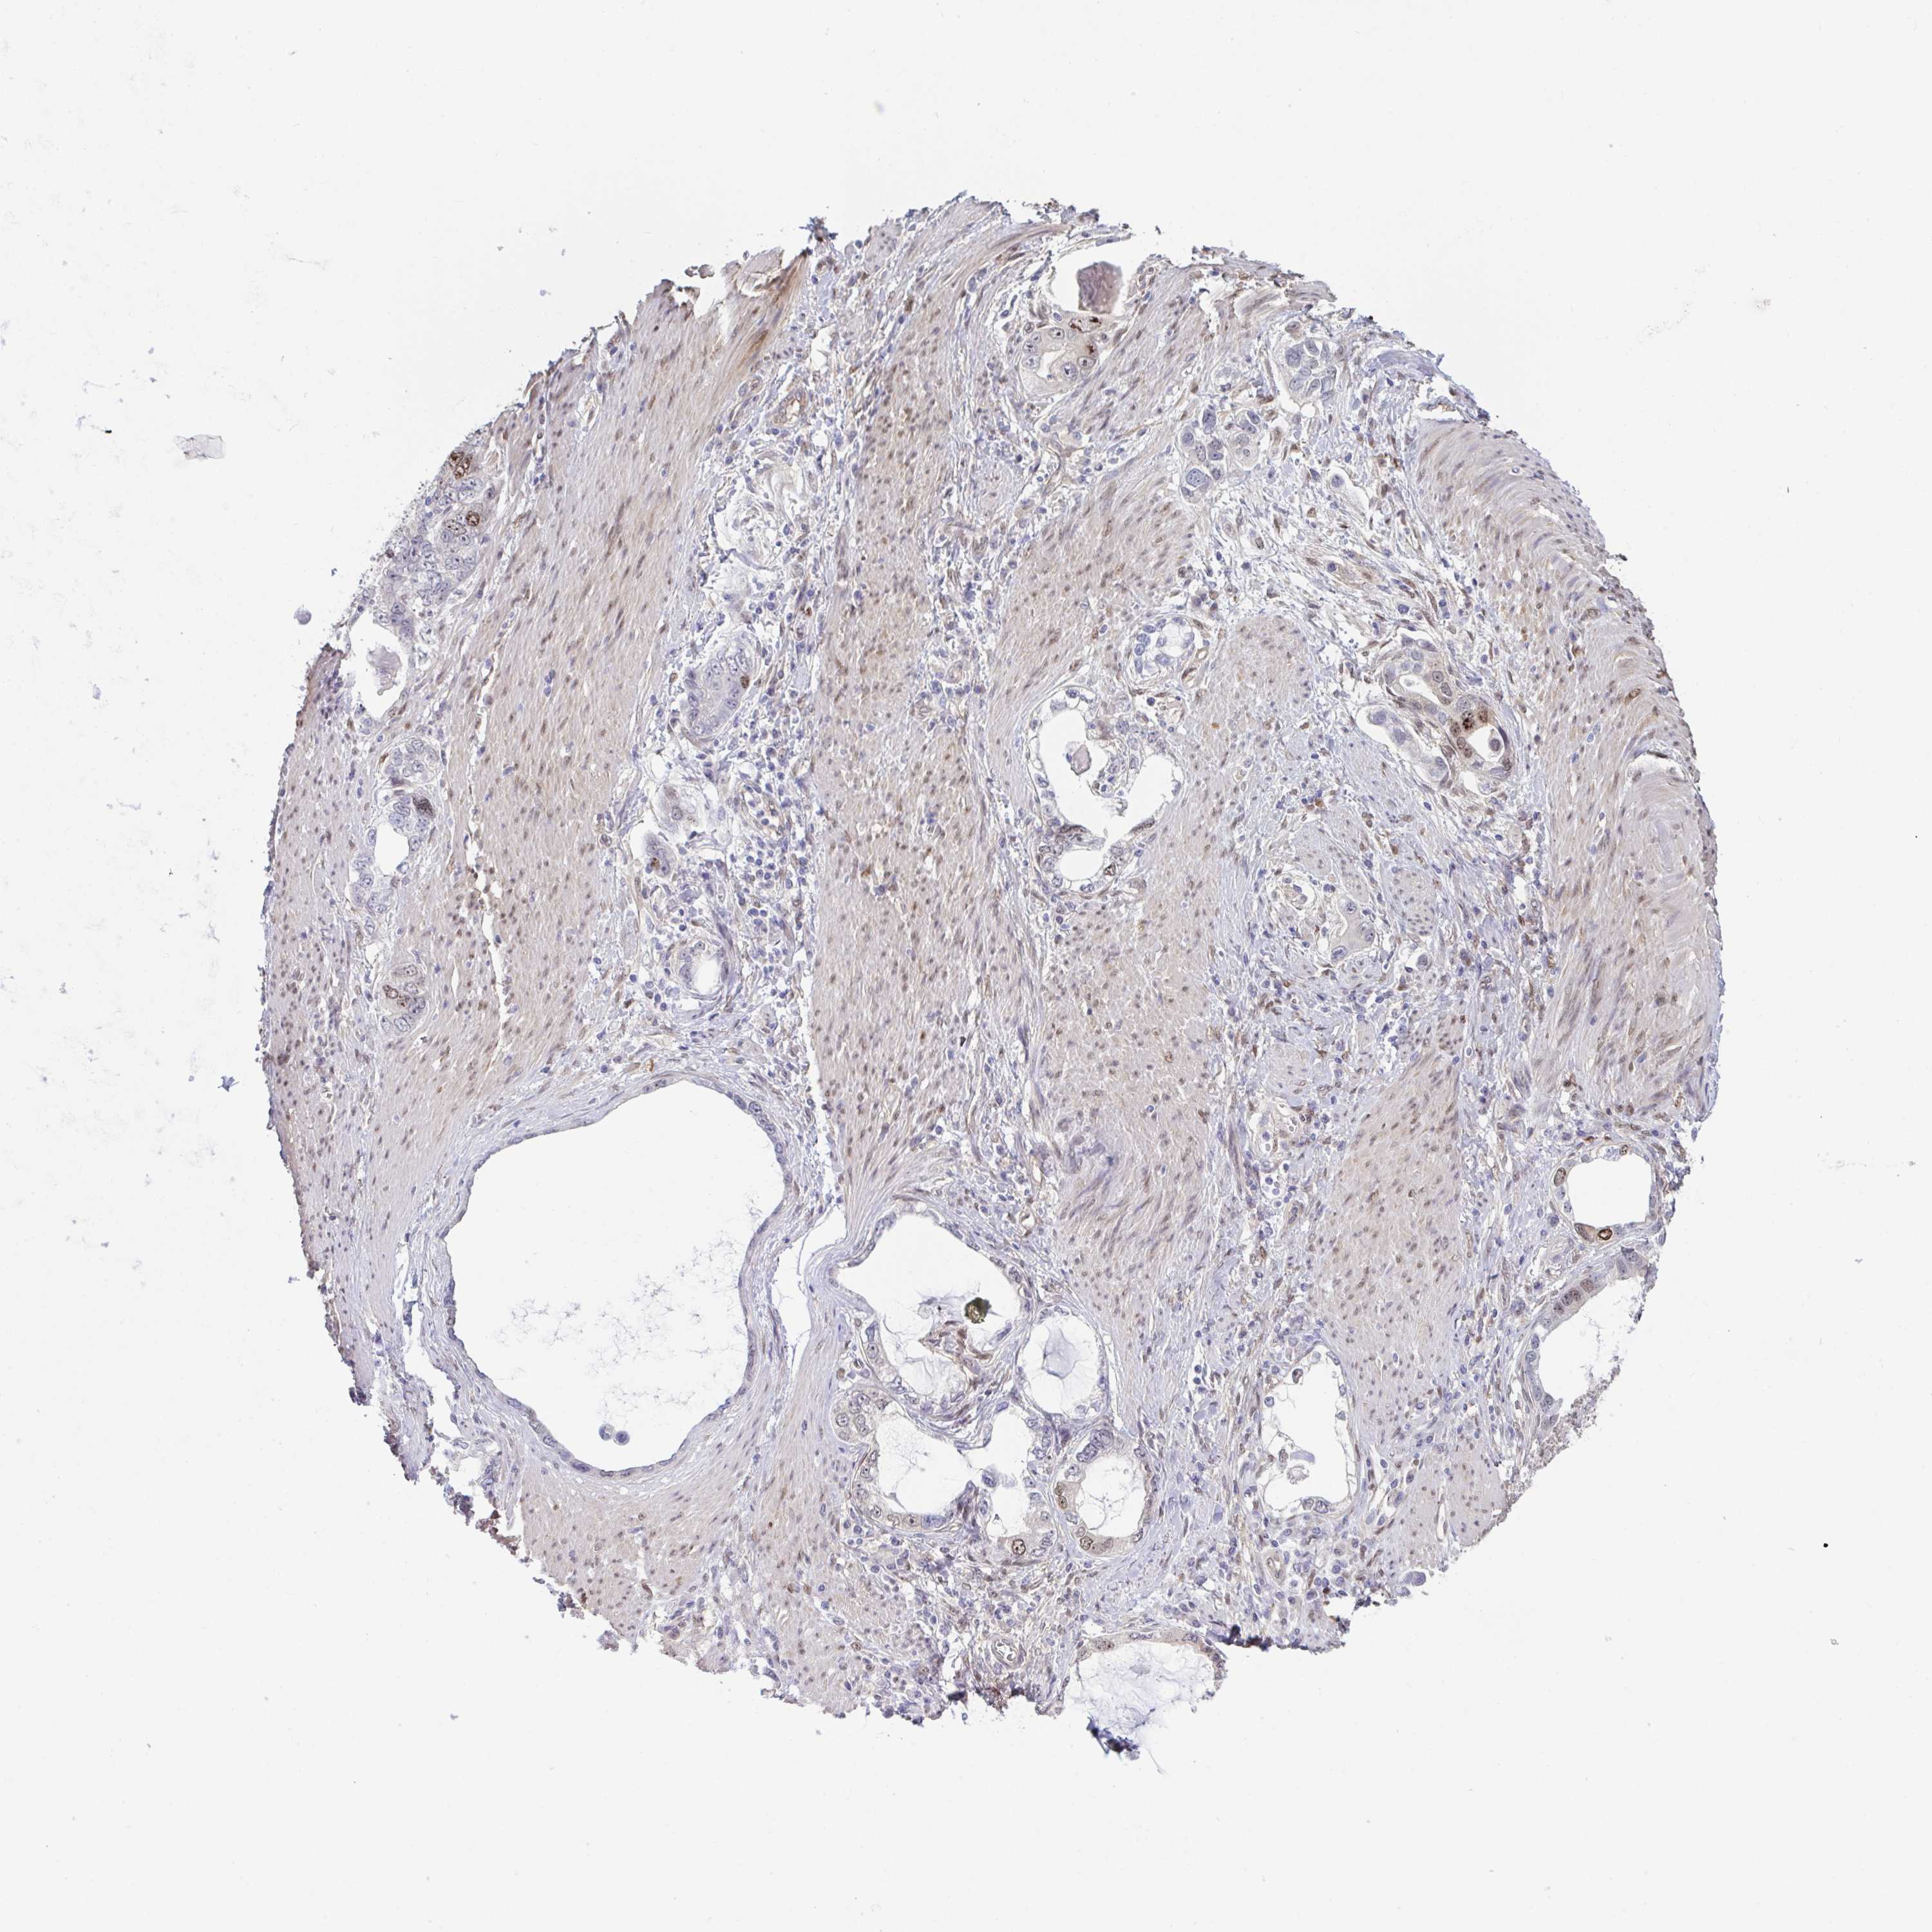

STOMACH CANCER - Protein expressioni

A mouse-over function shows sample information and annotation data. Click on an image to view it in a full screen mode. Samples can be filtered based on level of antibody staining by selecting one or several of the following categories: high, medium, low and not detected. The assay and annotation is described here.

Antibody stainingi

Antibody staining in the annotated cell types in the current human tissue is reported as not detected, low, medium, or high, based on conventional immunohistochemistry profiling in selected tissues. This score is based on the combination of the staining intensity and fraction of stained cells.

Each image is clickable and will lead to virtual microscopy that enables deeper exploration of all samples and also displays staining intensity scores, fraction scores and subcellular localization as well as patient and tissue information for each sample.

Antibody HPA058111

Staining

High

Medium

Low

Not detected

Intensity

Strong

Moderate

Weak

Negative

Quantity

>75%

75%-25%

<25%

None

Location

Nuclear

Cytoplasmic/membranous

Cytoplasmic/membranous,nuclear

Adenocarcinoma, NOS